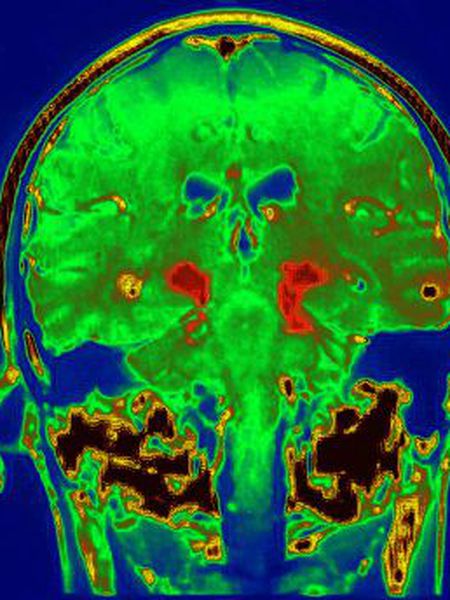

“Estudamos o cérebro após a morte em profundidade e com muitos detalhes. Mas, além disso, também acompanhamos a recuperação da funcionalidade dos demais pacientes, que estão vivos, e temos provas positivas, com imagens de PET [tomografia por emissão de pósitrons] de que os transplantes estão funcionando”, explica Isacson.